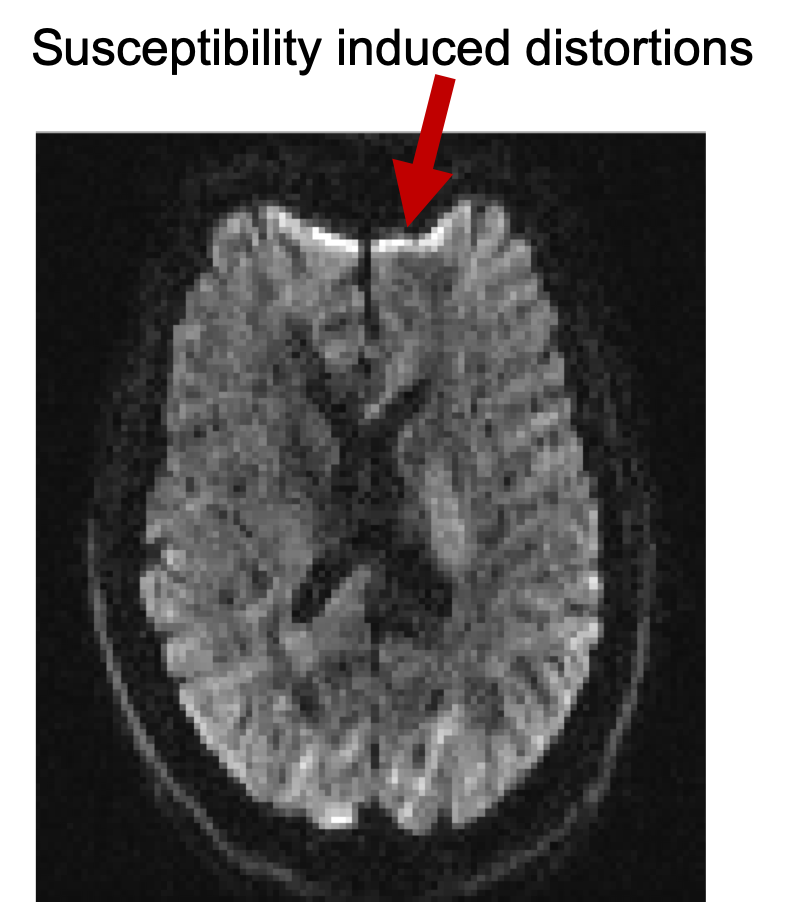

Susceptibilty induced distortions

Bring up fsleyes and open b1500.nii.gz - you will need to reset the maximum display range to around 2000. This is the diffusion data of the b=1500 shell before correction for distortions and it is a 4D image. Turn on movie mode (). Look at the sagittal slice and note the movement between volumes caused by eddy current-induced distortions. The reason you see this as a "movement" is that each volume is associated with a different diffusion gradient, and hence different distortions. This particular subject happened to lie very still, but in general you would also see "movement" due to actual subject movement. Notice also the susceptibility-induced distortions at the frontal part of inferior slices.

Open nodif in FSLeyes and have a look at different slices. Notice that as you go to more inferior slices, the frontal part of the brain starts to appear distorted (e.g. "squashed" or "elongated"). These distortions are always present in EPI images and are caused by differences in the magnetic susceptibilities of the areas being imaged.